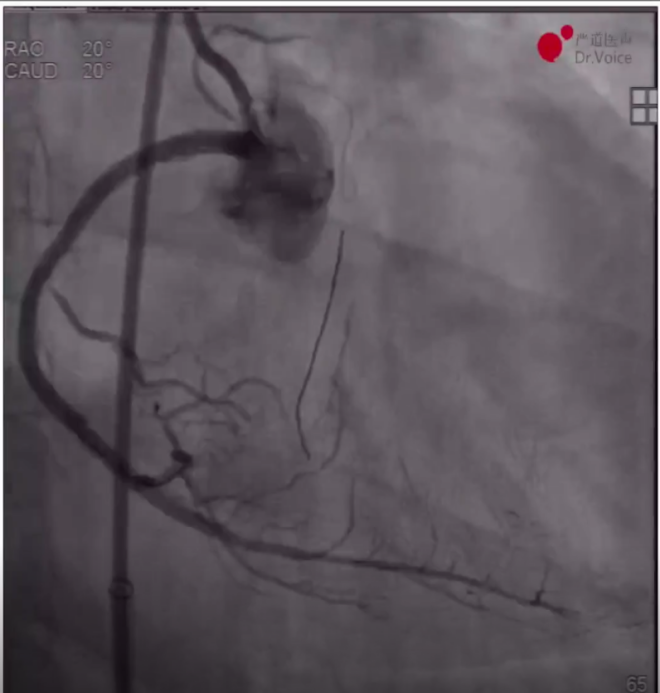

1、术前造影显示LAD近中段弥漫病变,LCX中段完全闭塞,RCA近段完全闭塞、远端形成侧枝循环。

LAD、LCX造影结果

RCA远端侧枝循环

RCA近端完全闭塞